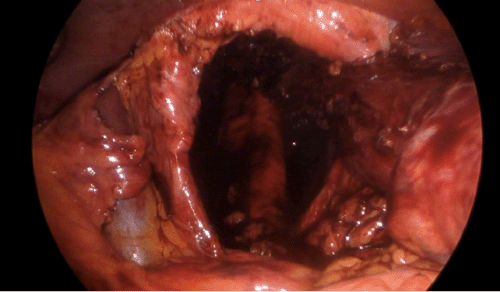

Preoperative evaluation included a computed tomography (CT) scan of the chest and abdomen, which demonstrated a large hiatal defect with extensive herniation of multiple abdominal organs—including the stomach, small bowel, large bowel, and pancreas—into the mediastinum (Figure 1). An upper gastrointestinal (UGI) series further characterized the defect as a type IV hiatal hernia, confirming an intrathoracic stomach complicated by organoaxial volvulus without evidence of acute outlet obstruction, and mild gastroesophageal reflux.

Figure 1. Preoperative CT Coronal View of Type IV Paraesophageal Hernia. Published with Permission